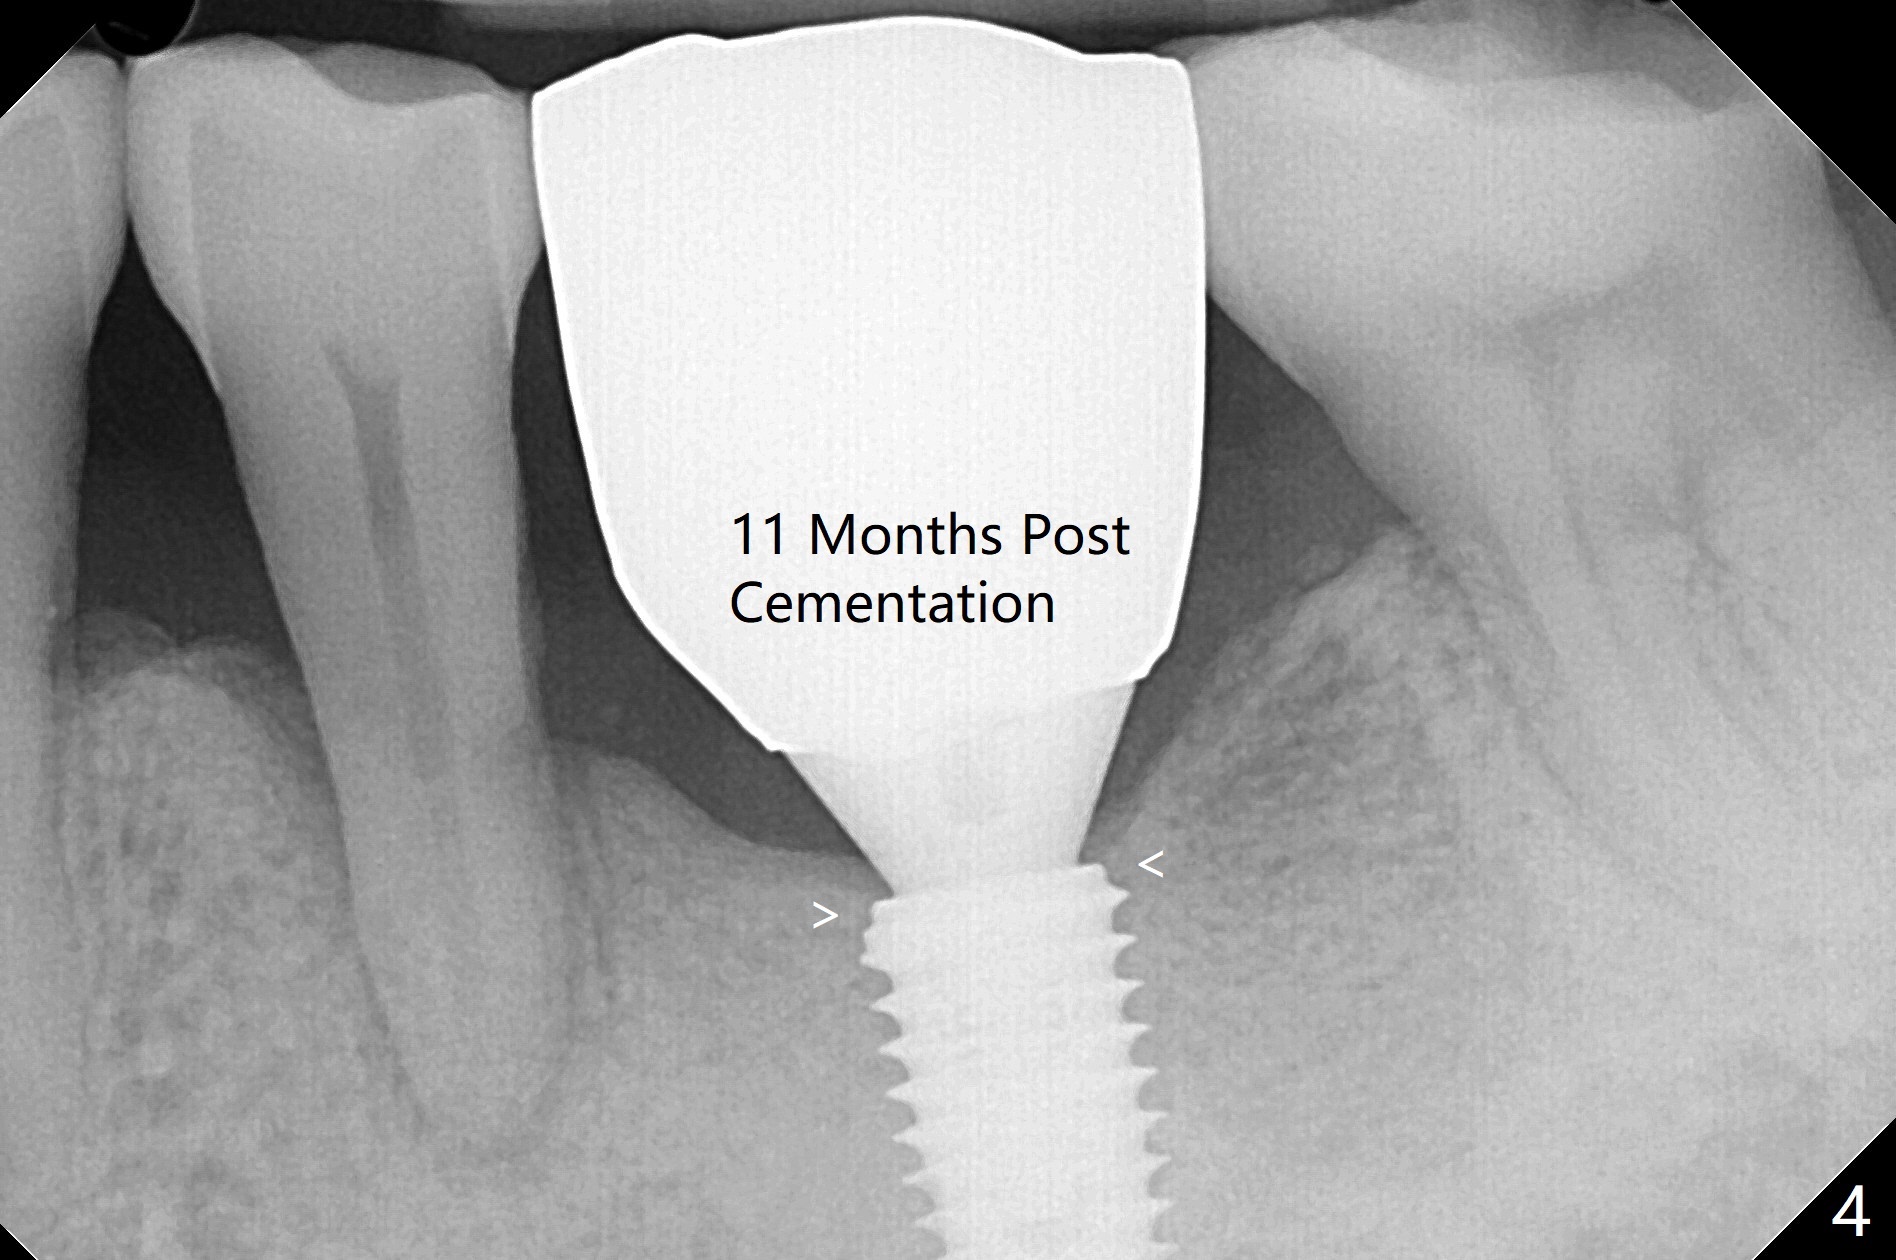

In fact the patient returns for impression 3 months 23 days postop; there is no bone loss at the crestal level (Fig.3). The patient returns 7 months post cementation. The access hole composite dislodges, but the abutment screw is tight, which is associated with the correct trajectory and guide. The crestal bone contacts the implant plateau 11 months post cementation (Fig.4 arrowheads).